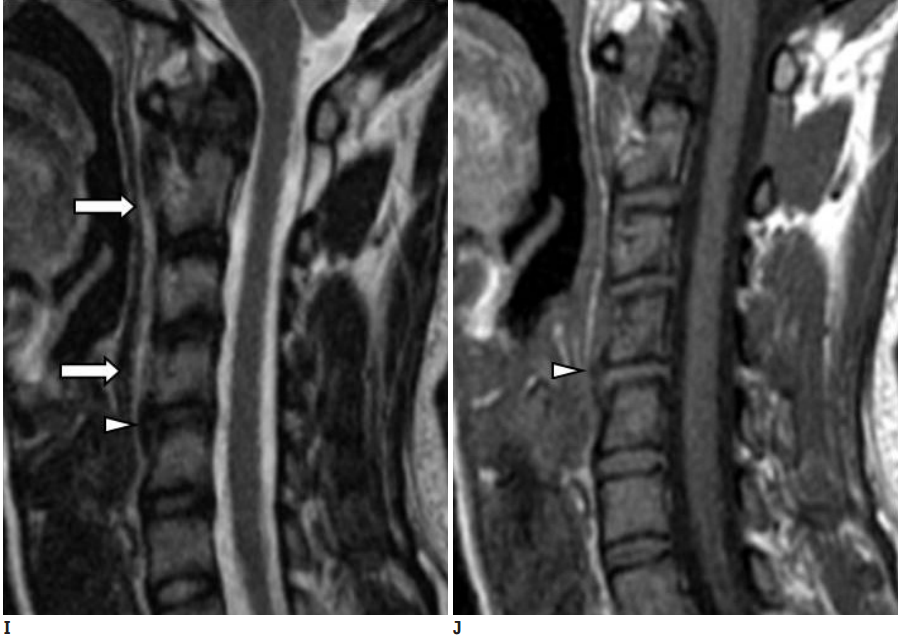

图:患者8岁,女孩,因严重颈部疼痛、活动受限伴左上肢无力、麻木不适2天就诊。既往有锁骨骨折、额部软组织挫伤病史。查体:颈椎活动受限,左上肢肌力正常,但感觉减退。白细胞、血沉、CRP升高。颈椎侧位片和CT平扫提示C6-7椎间盘钙化(粗箭头)和后纵韧带骨化(细箭头),颈椎MRI提示C6-7水平脊髓明显受压。给予颈椎制动、枕颌带2.5kg颈椎牵引2周。随后,颈托固定1个月。2年后随访复查颈椎CT如下图,同时上述症状完全缓解。

图:2年后复查CT示C6-7钙化的椎间盘和后纵韧带骨化都消失了

图:8岁女孩,因颈腰痛伴左上肢放射痛2月余就诊,颈椎侧位片、CT和MRI表现与上述病例类似。

图:给予保守对症治疗(具体不详)1月后症状消失。6个月时随访可见钙化的椎间盘和后纵韧带都消失了。